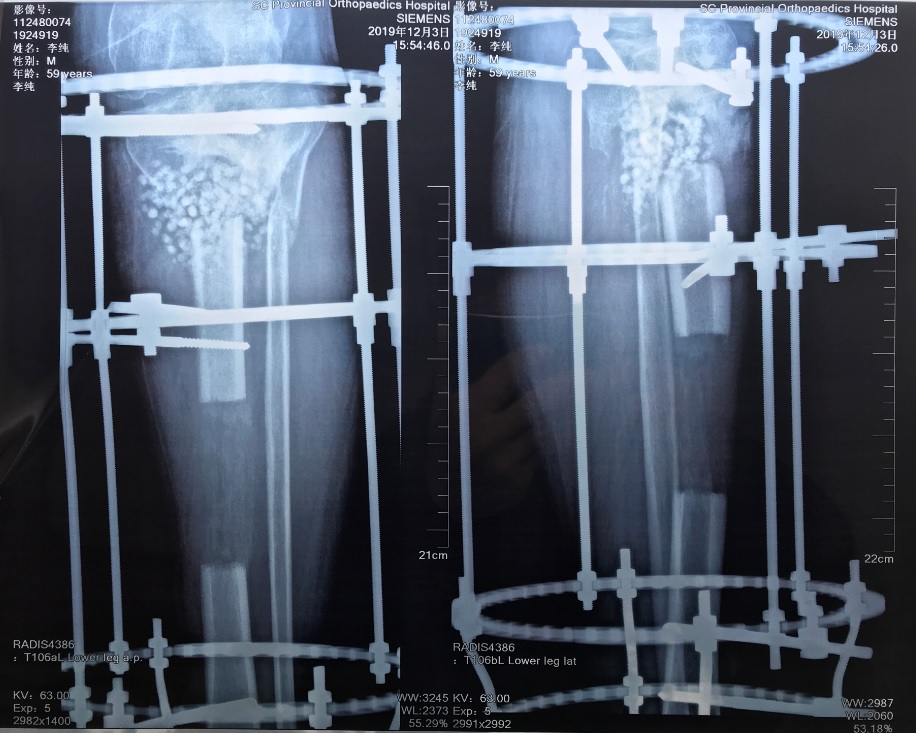

出院前X光片20191203_1554